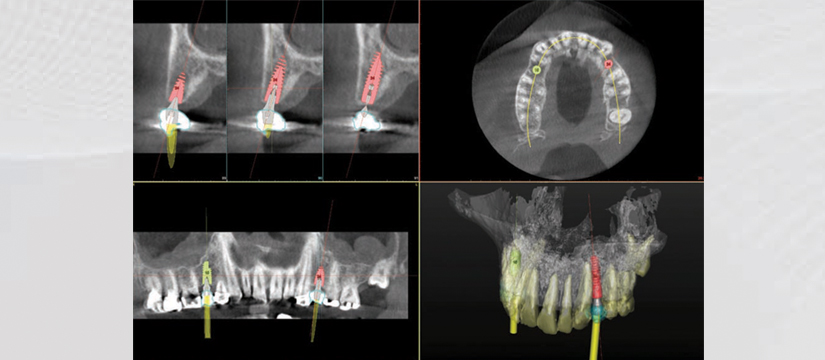

Klinika jonë premton se do t’ju ofrojë gjithnjë cilësinë më të lartë të shërbimit, me fjalën më të fundit të teknologjisë. Së fundmi ne jemi pajisur me pajisjen OWANDY IMAX TOUCH 3D. Kjo pajisje siguron me thjeshtësi dhe efikasitet imazhe high-definition për një diagnostikim të pagabueshëm. OWANDY është lideri i prodhimit të pajisjeve radiografike dentare në Francë, Amerikë, Gjermani e më gjerë. Produkti më i ri i OWANDY I-Max Touch 3D siguron të gjitha shërbimet radiografike në një aparaturë të vetme.

Aparatura posedon 17 programe të ndryshme ku mund të behën incizime si:

- 3D Dentare